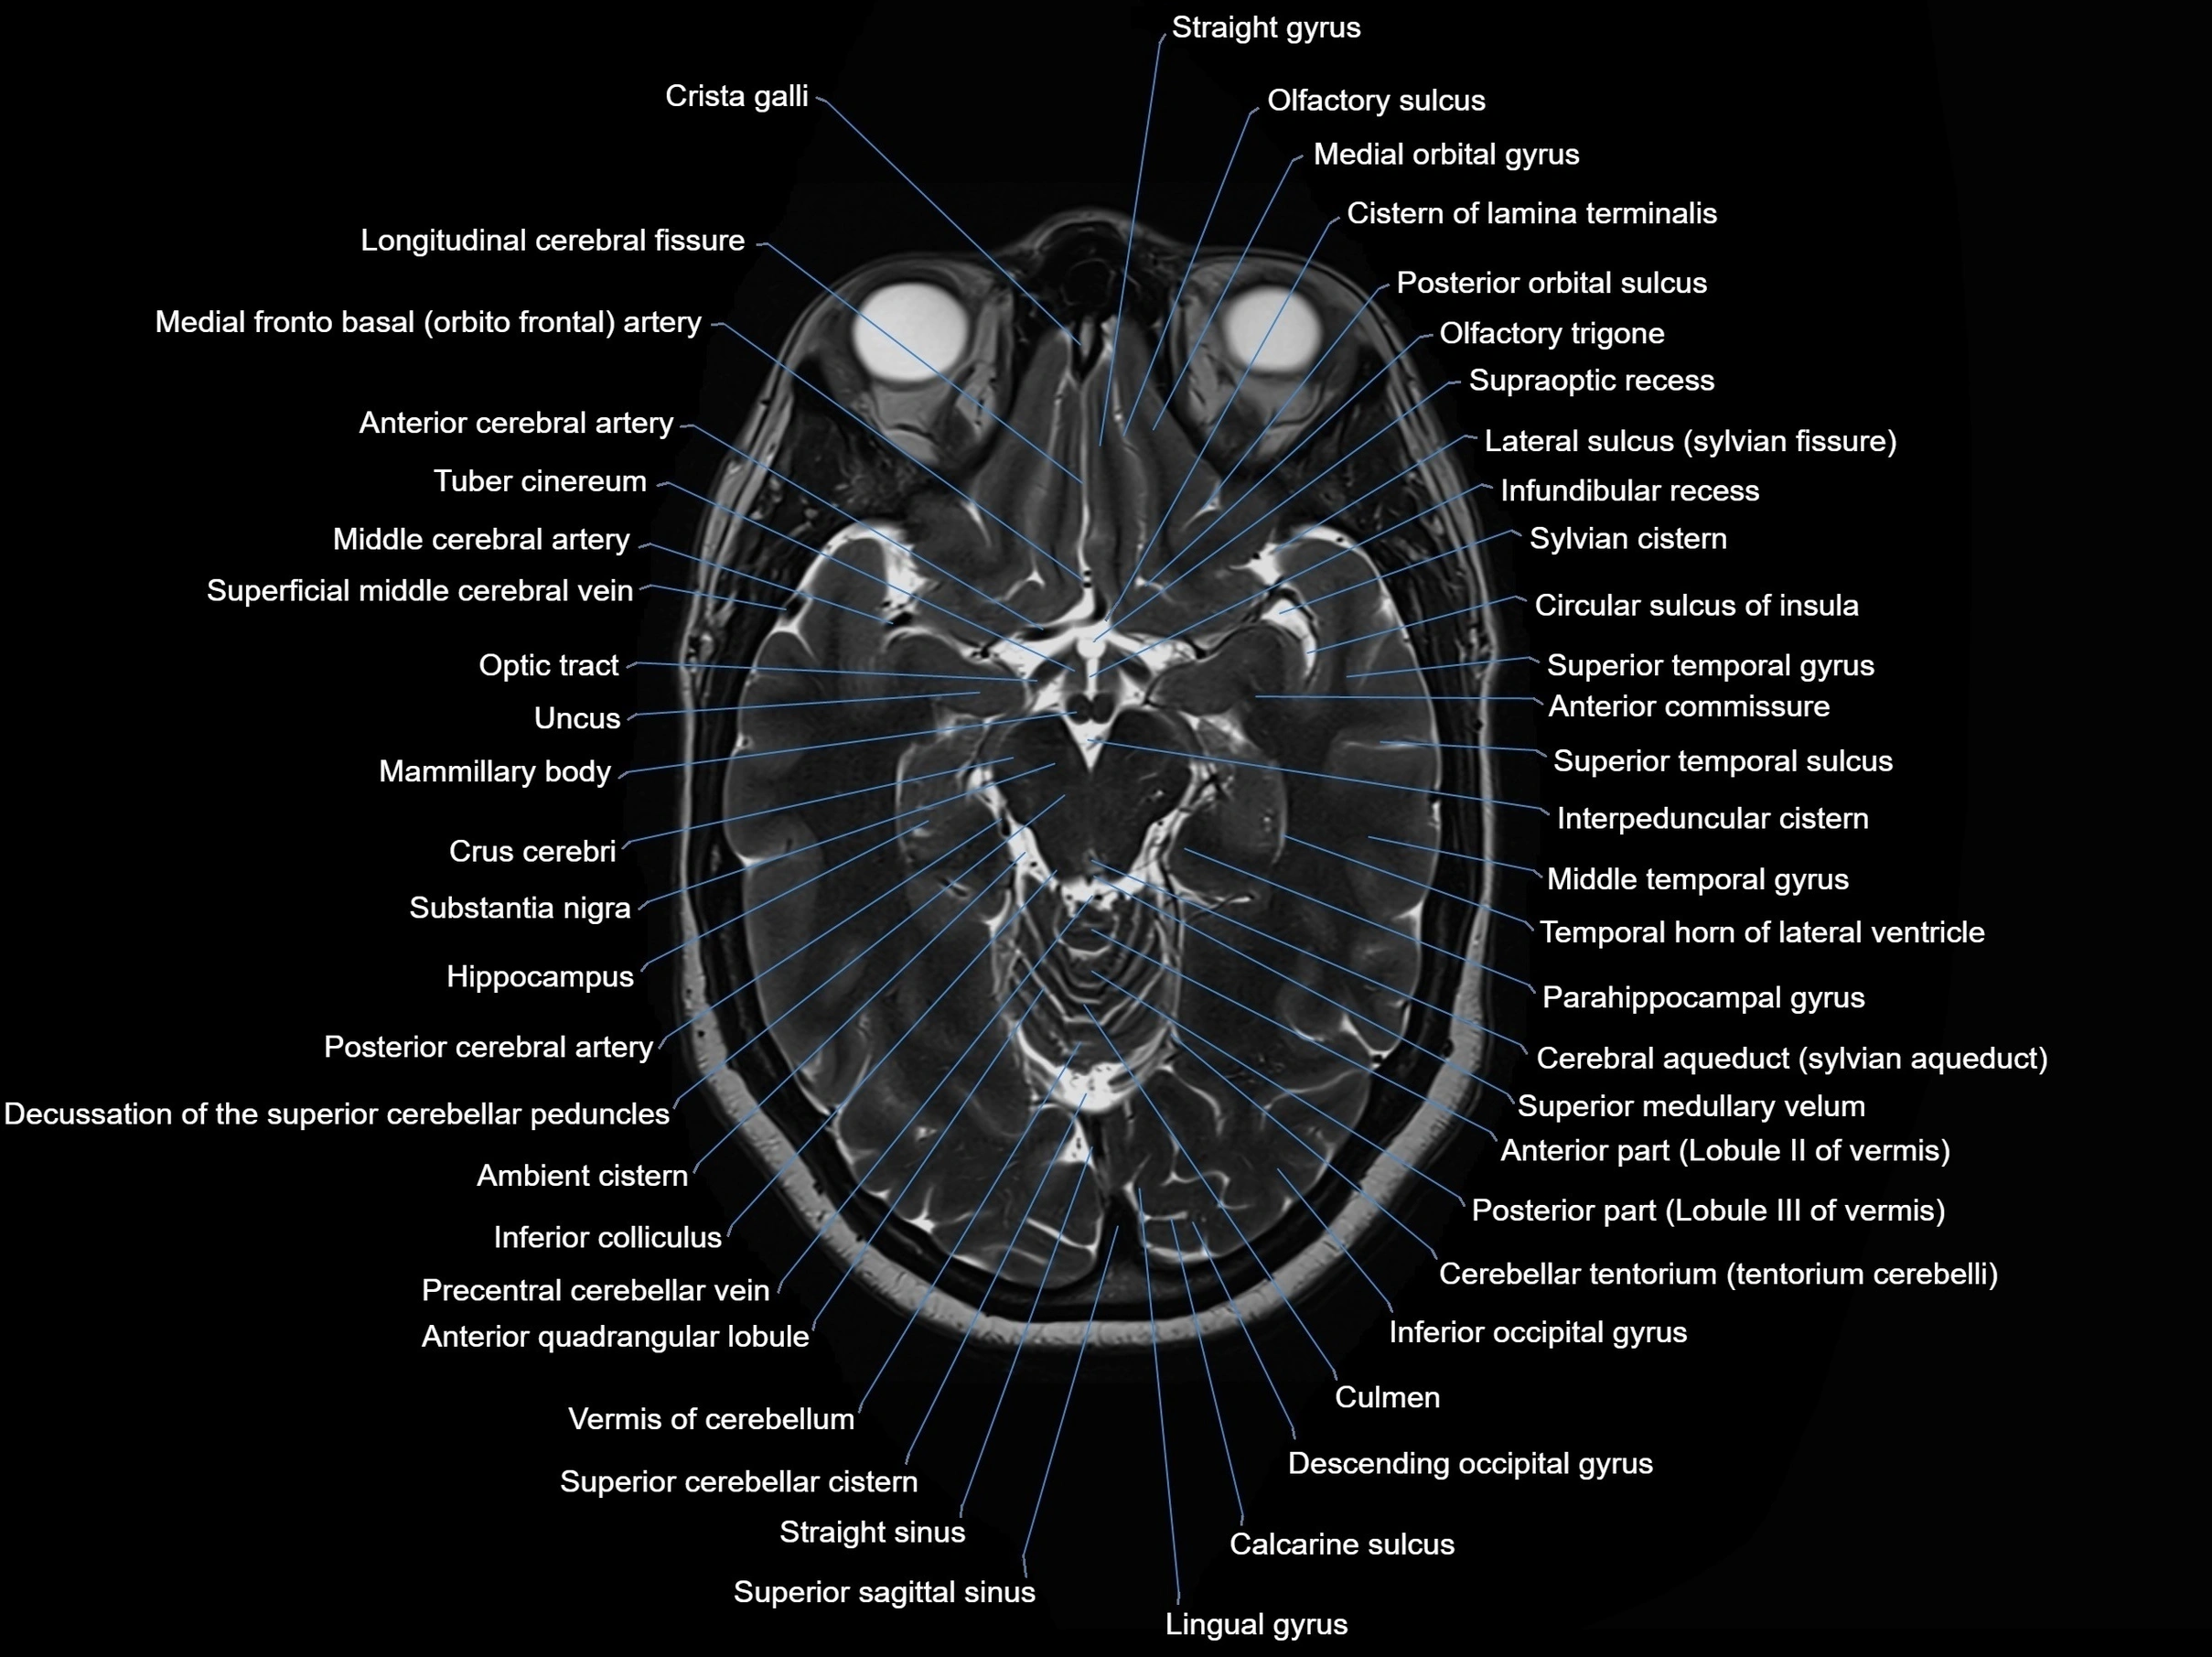

- Anterior cerebral artery

- Anterior commissure

- Cerebral aqueduct

- Cistern of lamina terminalis

- Crista galli

- Crus cerebri

- Culmen

- Decussation of the superior cerebellar peduncles

- Descending occipital gyrus

- Inferior colliculus

- Interpeduncular Cistern

- Lingual gyrus

- Longitudinal cerebral fissure

- Mammillary body

- Medial orbital gyrus

- Middle cerebral artery

- Middle temporal gyrus

- Olfactory sulcus

- Olfactory trigone

- Optic tract

- Parahippocampal gyrus

- Posterior cerebral artery

- Precentral cerebellar vein

- Straight sinus

- Substantia nigra

- Superior cerebellar cistern

- Superior sagittal sinus

- Supraoptic recess

- Sylvian cistern